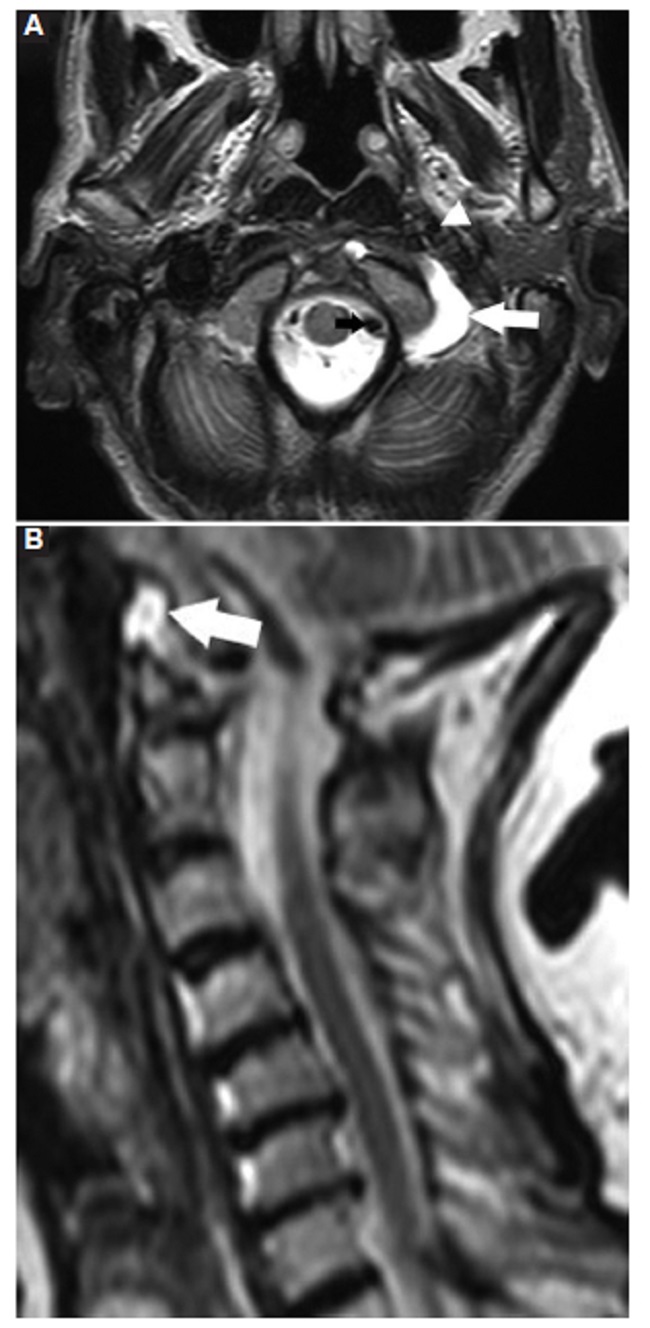

El segundo caso corresponde a un varón de 59 años, sin antecedentes de importancia asociados a su clínica, que consulta por parestesias intermitentes en el miembro superior izquierdo asociadas a cervicalgia. La RM mostró protrusión discal posterocentral en C5-C6 y DAAO izquierdo (Fig. 2).

La presencia de DAAO es un hallazgo inusual, bien valorado en la RM con cortes axiales ponderados en T2/STIR con supresión grasa, objetivándose como una colección semilunar hiperintensa, adoptando una morfología en C, rodeando al cóndilo occipital, entre la arteria carótida interna ventralmente y la arteria vertebral dorsalmente.